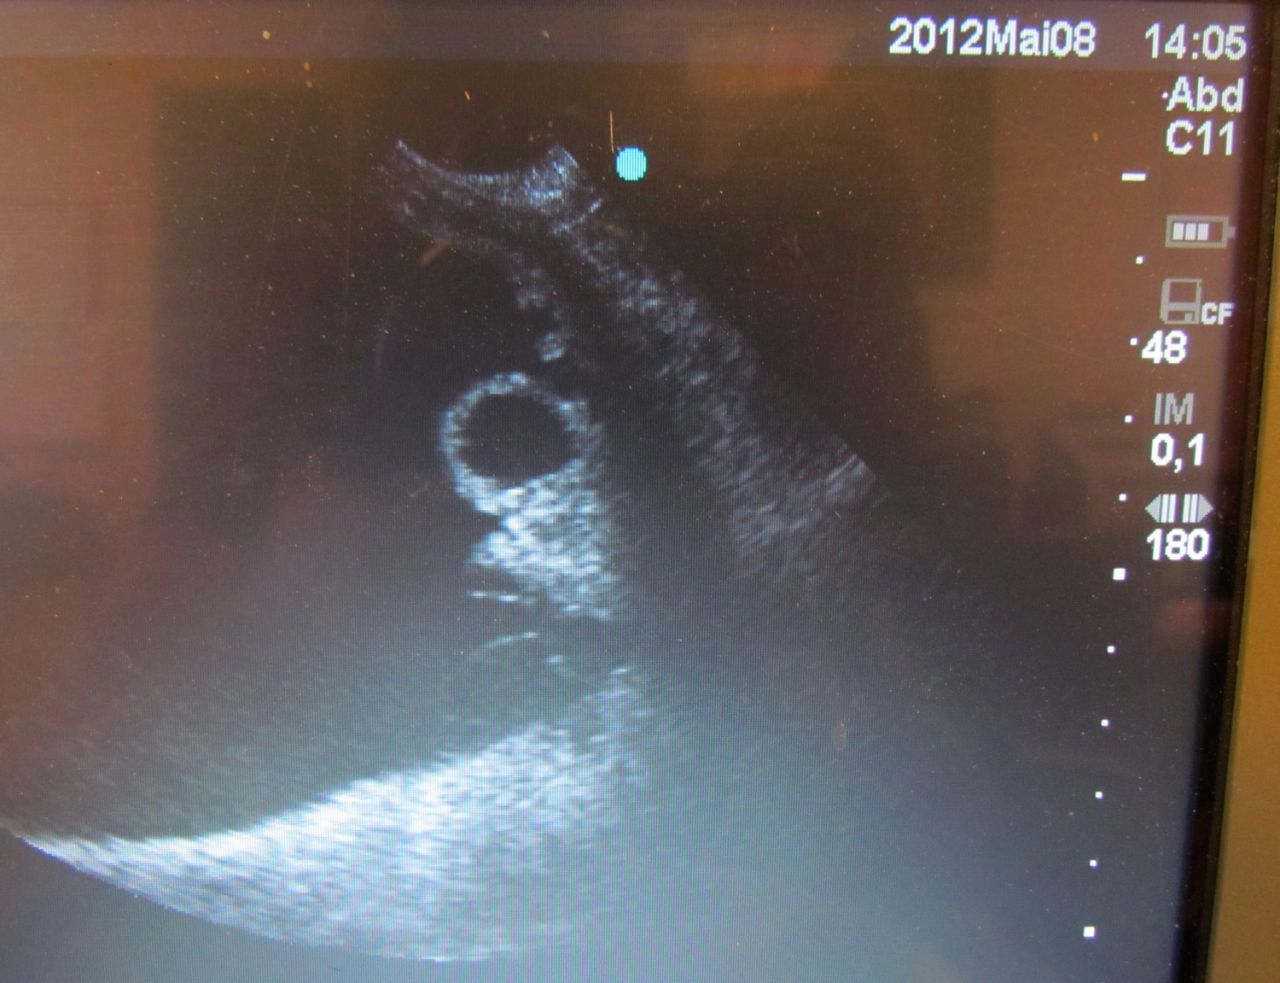

| Dire merci | à votre avis, mâle ou femelle? ![]() ![]() |

| Dire merci | J suis nulle avec ces sondes là! Mais bizarre qu'il n y ait pas de "gris" autour... |

Par al : le 11/05/12 à 09:05:35

| Dire merci | tu veux parler de tout ce fouilli? (qu'on voit en balayant un poil, c'est presque le même endroit en fait) |

Par al : le 11/05/12 à 09:05:45